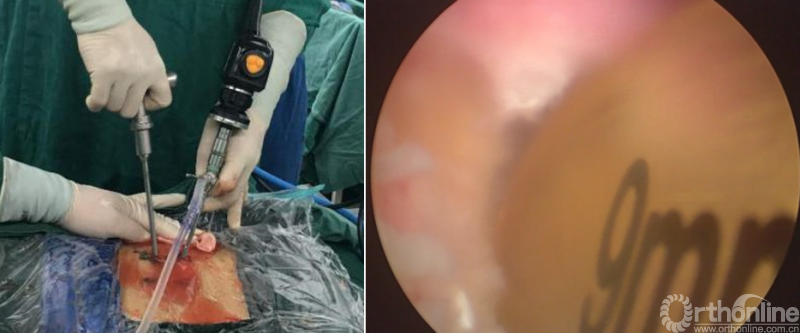

PE-PLIF技术十步法

详细步骤:一定、二辨、三凿、四分、五咬、六切、七旋、八铰、九填、十置

第一步“定”:X线定位在上位椎体下关节突下三分之一部;

第二步“辨”:镜下辨别下关节突关节囊;

第三步“凿”:凿除部分下关节突,显露上关节突及黄韧带;

第四步“分”:分离上关节突及黄韧带;

第五步“咬”:咬除部分上关节突,显露椎间盘及神经根;

第六步“切”:切除椎间盘;

第七步“旋”:旋转舌形套管保护神经根;

第八步“铰”:盲视下可撑开铰刀置入,撑开并处理上下终板;

第九步“填”;椎间隙填塞植骨;

第十步“置”:置入融合器、经皮钉。